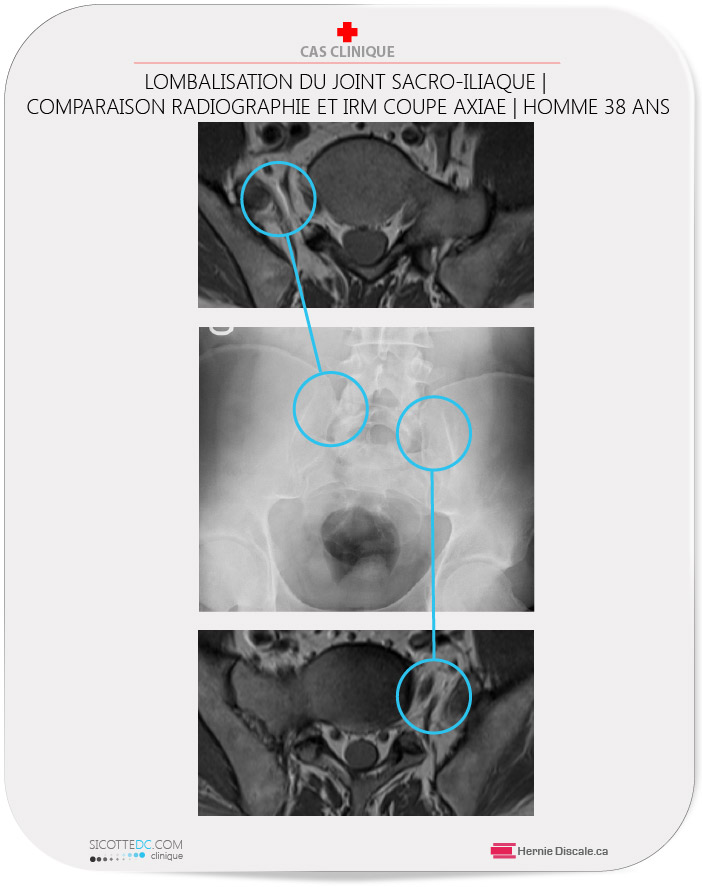

Cette patiente nous consulte pour des douleurs lombaires et sacro-iliaques. L’étude de l’IRM démontre deux particularités : un disque intervertébral anormalement développé à la vertèbre S1 (première vertèbre sacrée) et une géométrie anormale des corps vertébraux. Après analyse de la coupe axiale de l’IRM (voir image ci-haut), on aperçoit un joint supplémentaire autre que le joint sacro-iliaque.

Nous soupçonnons une anomalie de type segment transitionnel. Nous demandons des radiographies pour confirmer le diagnostic.